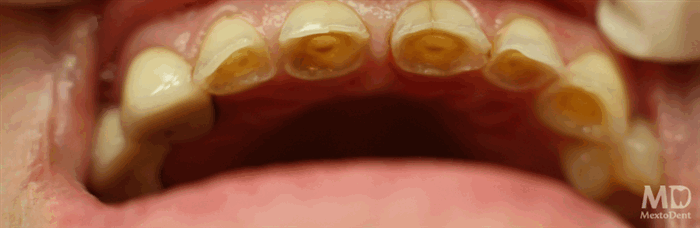

При кариесе ощущается запах изо рта, наблюдается изменение цвета зубов и недостаточное слюноотделение, острая боль, разрушение эмали и дентина.

Кариес — распространенная стоматологическая патология, затрагивающая твердые ткани. Во время патологического процесса из эмалевого покрытия вымывается жизненно важный элемент — кальций. Это приводит к разрушению эмали, образованию патогенных полостей, а затем воспалению пульпы и соединительной ткани, удерживающей зуб. Отсутствие терапии грозит не только полной потерей зуба, но и развитием сопутствующих болезней, опасных для жизни.

Для первой стадии характерно образование светло-желтого пятна на эмалевом покрытии. На этом этапе пациент, как правило, не чувствует дискомфорта.

При средней стадии начинается разрушение не только эмалевого покрытия, но и дентина — более мягкой ткани. Затягивать с лечением нельзя, так как кариес стремительно поражает глубокие структуры. Чаще всего при средней стадии внешние патологические изменения незначительны — отмечается потемнение эмали в области поражения, кариозные полости неглубокие, боли умеренные ноющего характера. У некоторых пациентов отмечается дискомфорт при контакте зуба с холодной или горячей пищей.

Глубокий кариес вызывает болезненность при употреблении сладких, кислых или соленых блюд, а также при воздействии на зуб низких или высоких температур. Если боль отступает через 15–20 минут после контакта с агрессивным фактором, это говорит о том, что болезнь не переросла в пульпит. В таком случае еще есть шанс спасти зуб с полным сохранением его функций.

Важно! Запущенные формы не всегда сопровождаются повреждениями эмали, хотя внутри зуба уже отмечаются серьезные разрушительные процессы. При таком течении один из главных симптомов — неприятный запах изо рта, который обусловлен гниением частичек пищи, скопившихся в полости.